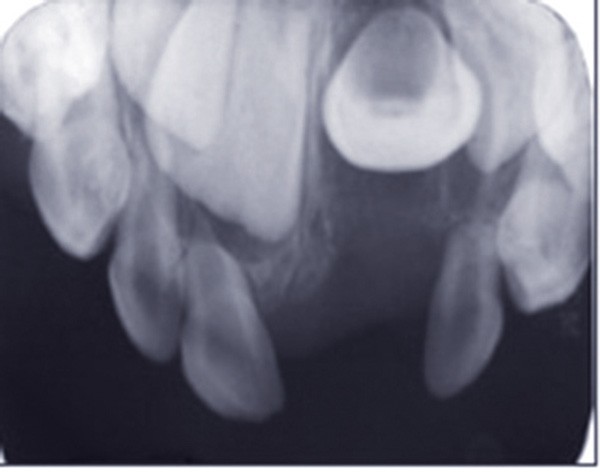

Les traumatismes des dents temporaires connaissent deux pics de fréquence entre 12 et 18 mois, et entre 3 et 4 ans. Ils interviennent donc souvent au cours de la croissance de l’appareil manducateur, avec de possibles conséquences sur le développement de celui-ci, et notamment sur les germes des dents définitives. C’est pourquoi le suivi des dents temporaires traumatisées jusqu’à la fin de la croissance est indispensable. Parmi les étapes qui doivent être surveillées, figure en premier lieu la formation de la dent définitive, qui sera surveillée radiographiquement. Son éruption peut également être perturbée par une dent temporaire traumatisée : le statut pulpaire de celle-ci sera surveillé cliniquement et radiographiquement. En effet, le risque infectieux subsiste après le traumatisme, et le suivi permettra d’éviter des cas de cellulites sévères. Si elle est nécessaire, l’extraction de la dent traumatisée pourra ainsi être réalisée au moment opportun. Enfin, dès la consultation qui a lieu après le traumatisme, les parents doivent être informés de l’importance du suivi, afin qu’ils y participent activement (fig. 1 et 2).